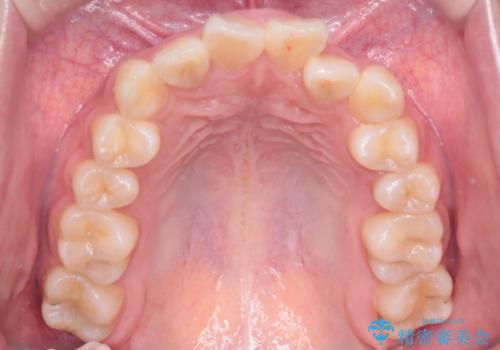

【インビザライン】前歯の凸凹を非抜歯で治療

- 前歯の凸凹を主訴の来院されました。

奥歯を後ろの方に移動させるために矯正用のアンカースクリューを使いながら治療をおこないました。

患者さんの都合により、マウスピースの装着時間が不足したため、途中からワイヤーにて治療を行いました。